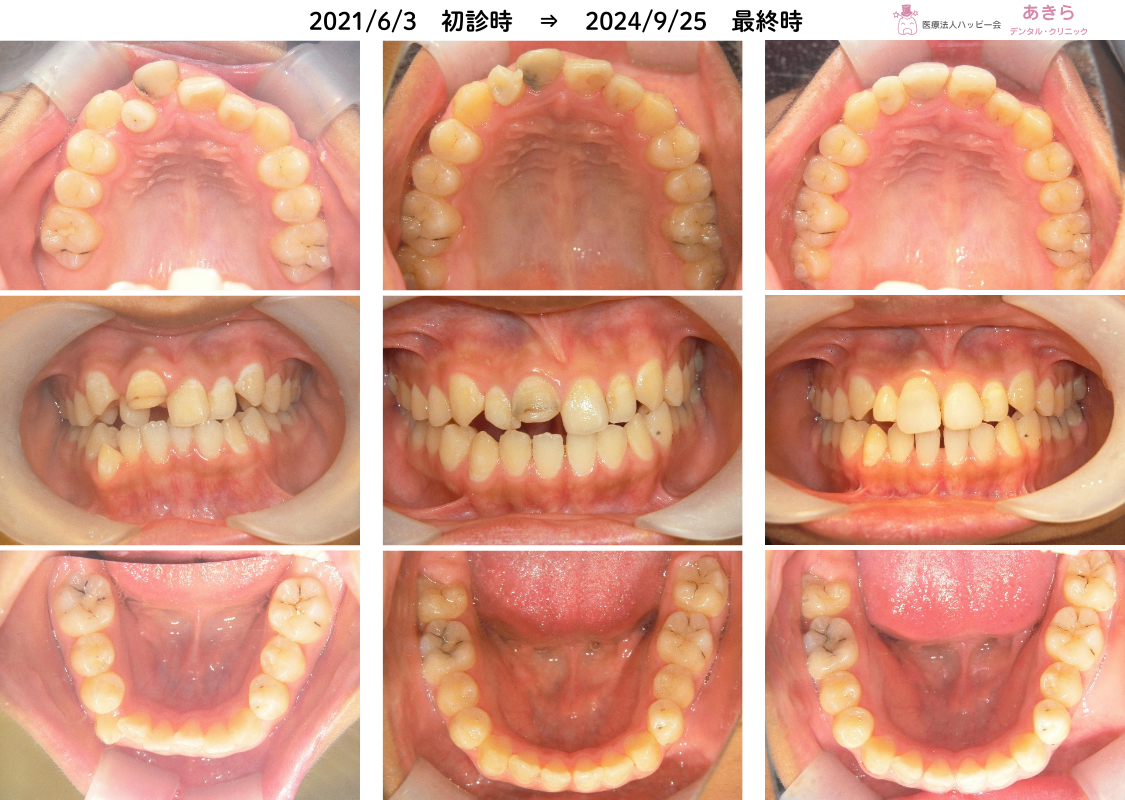

2021年6月3日 初診時 ⇒ 2024年9月25日 最終時

2021年6月3日 ⇒ 2024年9月25日

12歳4ヶ月 ⇒ 15歳7ヶ月

中1 ⇒ 高1

右上1番が外傷により失活歯となり、矯正治療で動きにくい可能性があること。

右上2番が矮小歯なので、矯正治療のみで前歯の審美をよくすることは難しいことを了承の上で治療を開始しました。

永久歯の抜歯をしないことを考慮し「SH療法」を開始しました。

- 経過観察をして最終資料採得を予定